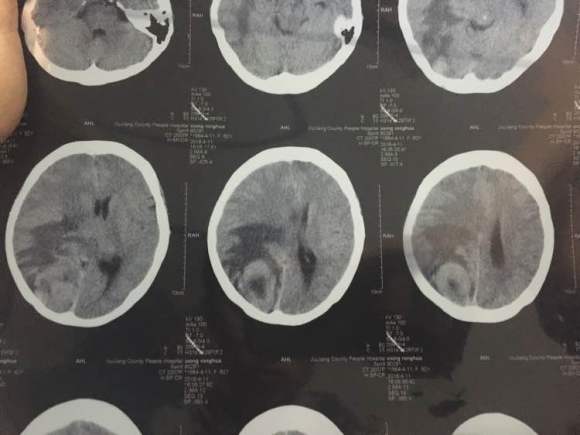

共1张

肾肿瘤肾癌,